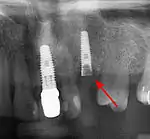

Long-term failures are due to either loss of bone around the tooth and/or gingiva due to peri-implantitis or a mechanical failure of the implant. Because there is no dental enamel on an implant, it does not fail due to cavities like natural teeth. While large-scale, long-term studies are scarce, several systematic reviews estimate the long-term (five to ten years) survival of dental implants at 93–98 percent depending on their clinical use.[1][2][3] During initial development of implant retained teeth, all crowns were attached to the teeth with screws, but more recent advancements have allowed placement of crowns on the abutments with dental cement (akin to placing a crown on a tooth). This has created the potential for cement, that escapes from under the crown during cementation to get caught in the gingiva and create a peri-implantitis (see picture below). While the complication can occur, there does not appear to be any additional peri-implantitis in cement-retained crowns compared to screw-retained crowns overall.[64] In compound implants (two stage implants), between the actual implant and the superstructure (abutment) are gaps and cavities into which bacteria can penetrate from the oral cavity. Later these bacteria will return into the adjacent tissue and can cause periimplantitis.